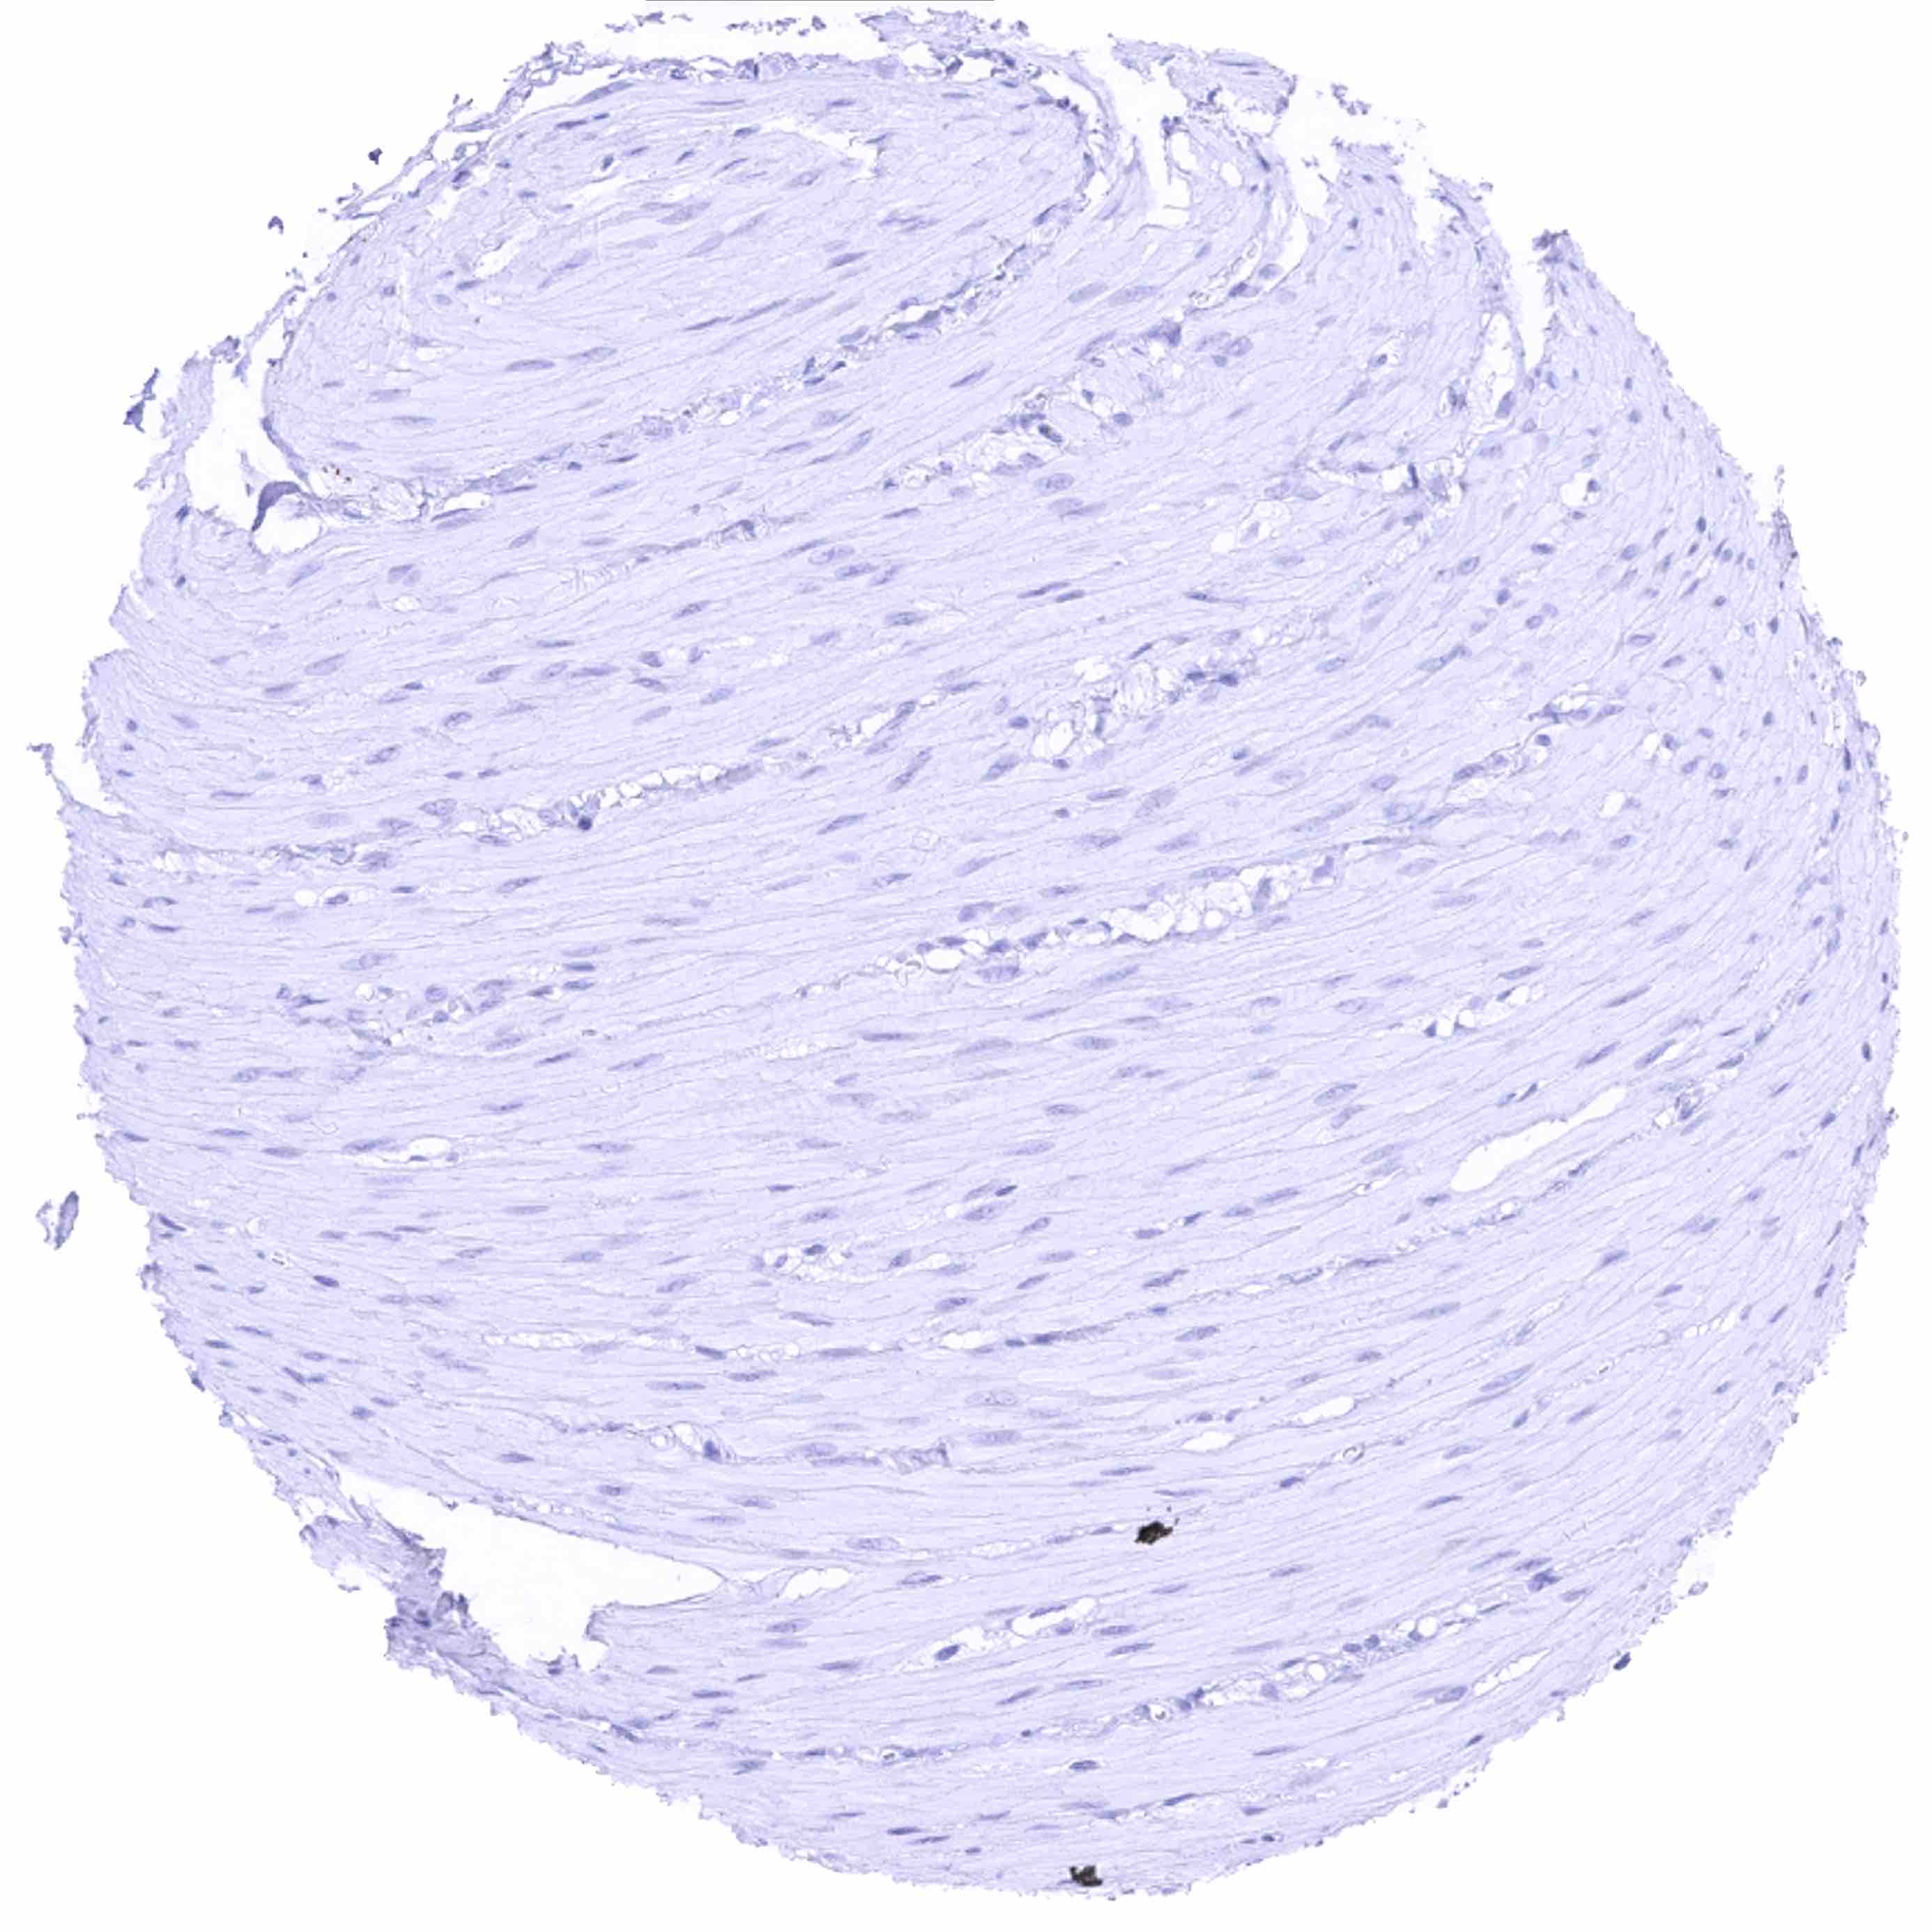

Aorta, media